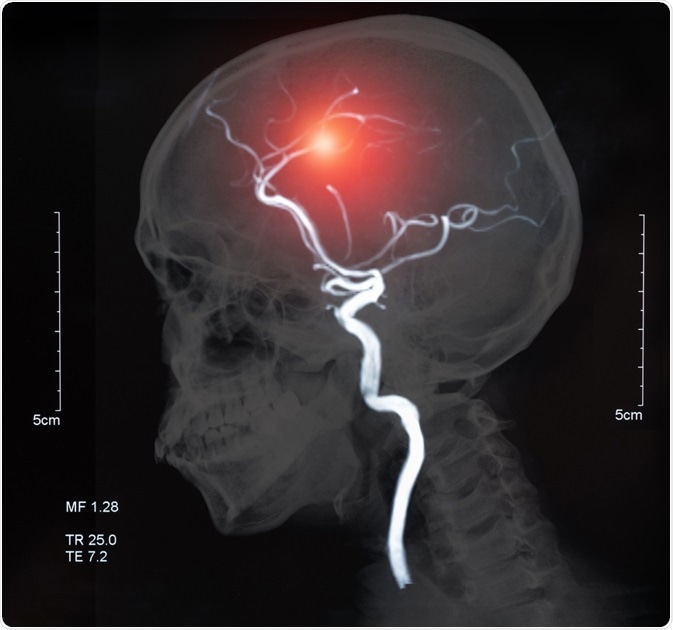

Cerebrovascular Disease

Image Credit: create jobs 51/Shutterstock.com

Diagnosis of the different types of cerebrovascular disease can be made through different neuroimaging tests. Cerebral angiography is used to visualize the arteries of the head and neck, which are not normally seen using an x-ray.